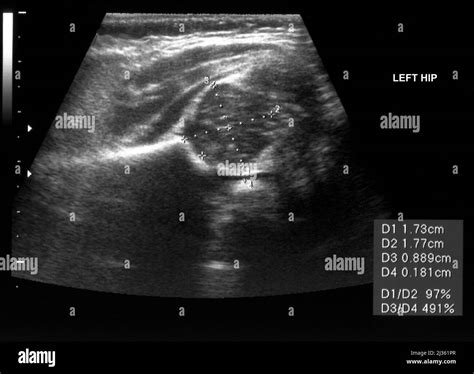

Interpreting the Results of an Infant Hip Ultrasound

The results of an Infant Hip Ultrasound are interpreted by a radiologist or orthopedic specialist who is trained in pediatric imaging. The images are evaluated for several key factors, including:

• The shape and depth of the acetabulum

• The position of the femoral head within the acetabulum

• The presence of any abnormalities or dislocations